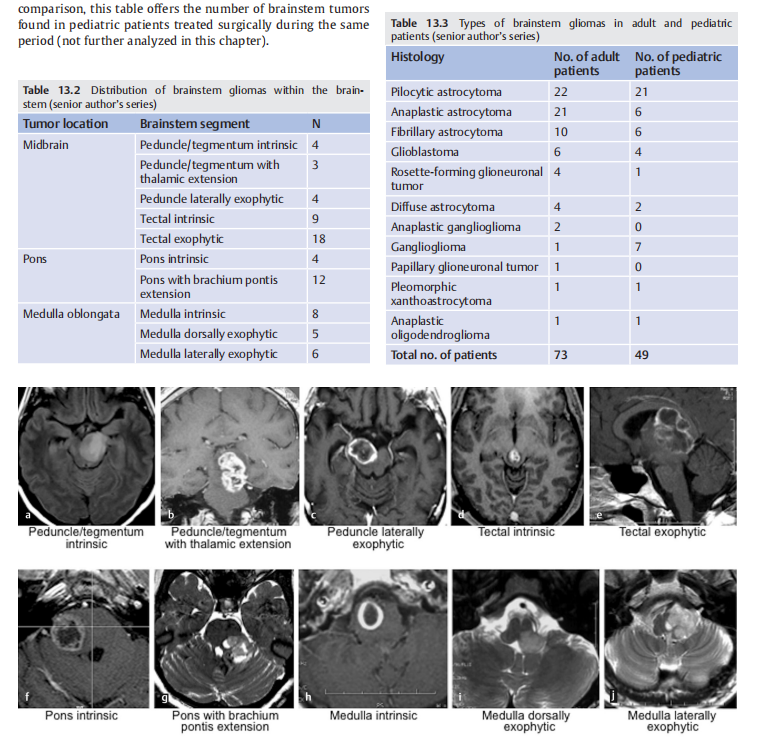

脑干胶质瘤占儿童所有脑肿瘤的20%,其病程普遍较差。相比之下,成人脑干胶质瘤是一种罕见疾病,仅占成人神经胶质脑肿瘤的1%至2%,这形成了一组具有不同预后的病变。

上图显示成人、儿童脑干胶质瘤的区别,其中成人脑干胶质瘤2年生存率>50%,而儿童脑干胶质瘤中,弥漫内生型脑干胶质瘤DIPG的2年生存率<25%,其他则>90%